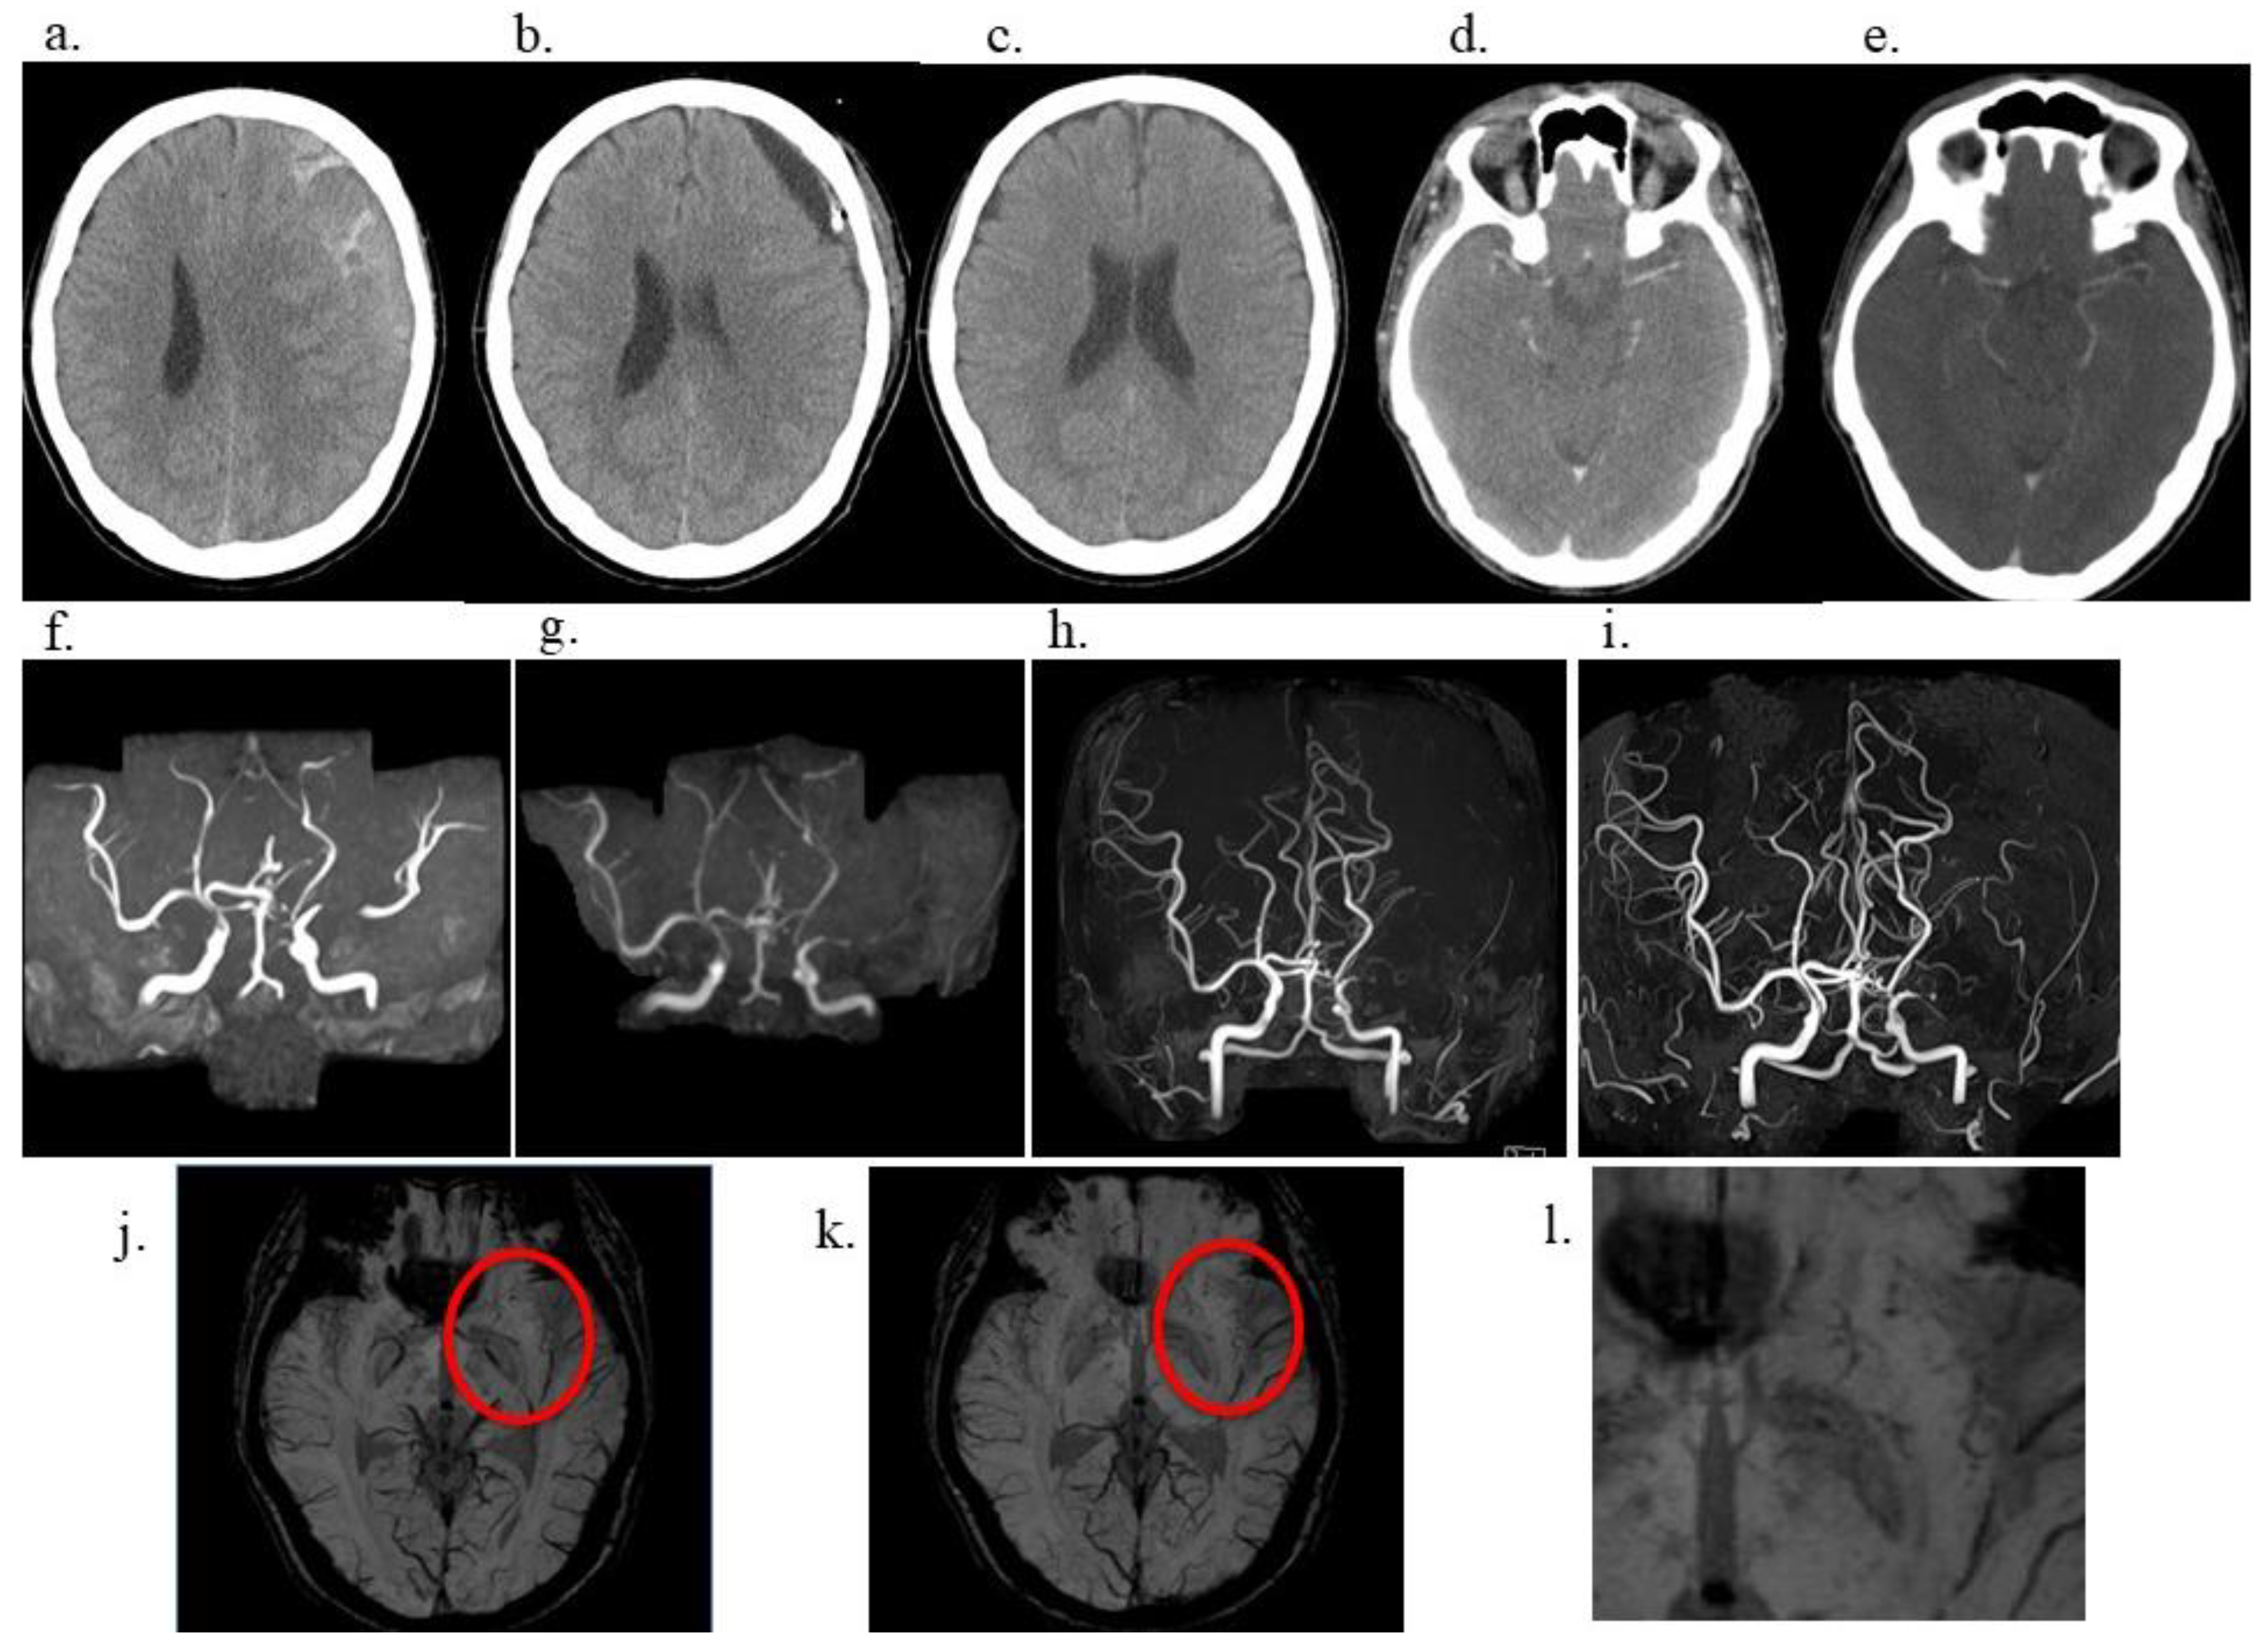

At the age of 53 years (13 years from CSDH), the patient remained neurologically stable, with an mRS score of 0 and no history of transient ischemic attacks or overt ischemic stroke. Resting single-photon emission computed tomography demonstrated a mild reduction (<5%) in cerebral blood flow on the affected side. Additionally, BPAS was performed to assess the arterial wall structure of the anterior circulation (Figure 2). Notably, the left MCA appeared remarkably thinner than the contralateral side, indicating a significant reduction in its outer diameter. These structural changes were not apparent on conventional time-of-flight (TOF)-MRA, underscoring the added value of BPAS for detecting subtle arterial wall abnormalities that may be difficult to distinguish from simple luminal stenosis on TOF-MRA alone.

Moyamoya syndrome is diagnosed in individuals who exhibit Moyamoya-like cerebrovascular changes in association with an identifiable underlying condition [2,6]. The present case is extremely rare because it involved unilateral progressive stenosis of the MCA and the development of abnormal vascular networks observed long-term following head trauma and surgical intervention for CSDH. Notably, BPAS was crucial in detecting outer diameter narrowing of the anterior circulation vessels, particularly the left MCA, which were not clearly visualized on conventional TOF-MRA, highlighting the complementary value of anterior circulation BPAS in evaluating subtle arterial wall changes and structural abnormalities in Moyamoya-like conditions.

Here, conventional TOF-MRA was limited in visualizing the fine vascular structures within the anterior circulation. Nonetheless, anterior circulation BPAS [5] provided a clear delineation of the outer contours of the left MCA, revealing a notable reduction in outer diameter and confirming the presence of subtle yet significant vascular narrowing. BPAS imaging may be particularly advantageous for detecting changes in the vessel wall and identifying hypoplastic or structurally compromised arteries that may be difficult to evaluate with conventional luminal imaging techniques, such as TOF-MRA. In this case, BPAS allowed for the detection of fine collateral vessels and better characterization of the affected segment, potentially indicating a Moyamoya-like vasculopathy diagnosis rather than simple atherosclerotic stenosis. The ability of BPAS to complement MRA by highlighting extracranial vessel morphology may offer important diagnostic value, especially in atypical cases such as unilateral Moyamoya syndrome or secondary vascular changes following trauma or surgery. Therefore, this imaging approach may aid in early detection, differentiation, and longitudinal monitoring of Moyamoya-related cerebrovascular changes.

Figure 2. Anterior circulation basi-parallel anatomical scanning (BPAS) revealing unilateral arterial outer diameter narrowing. BPAS imaging demonstrates marked narrowing of the left middle cerebral artery outer diameters (red arrows) compared to the right side (yellow arrows), not clearly visible on time-of-flight magnetic resonance angiography, suggesting arterial wall involvement beyond simple luminal stenosis. .